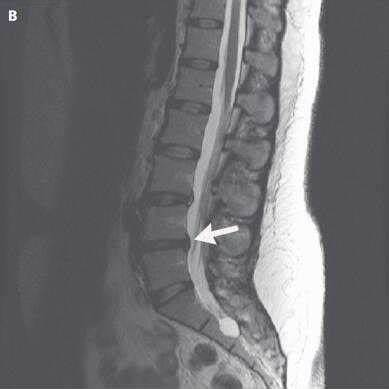

果不其然,老陈在医生的安排下,做了一个腰椎的磁共振检查,检查出来确实存在腰椎间盘突出,而且神经也受到了压迫。

初步考虑由于腰椎脊髓神经受压迫,导致控制下肢膝关节处的神经感觉异常,出现膝关节的疼痛......感觉这终于找到了老陈膝关节疼痛的原因了。

但脊柱骨科的医生,看完老陈的腰椎磁共振片子后,结合老陈的病史及相关骨科查体,考虑老陈的腰椎间盘突出压迫神经,不至于引起如此严重的症状。